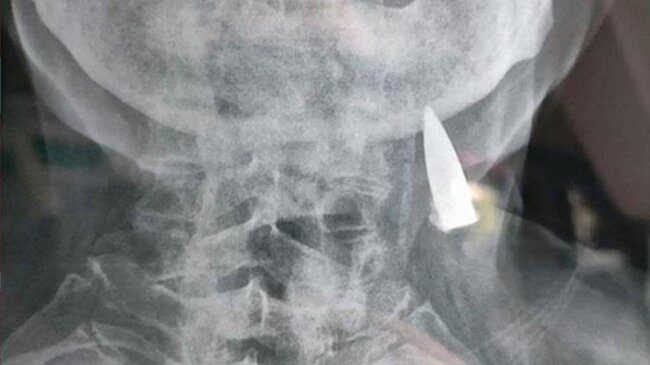

Çinli 95 yaşlı Zhao He adlı kişi 25 yaşında İkinci Dünya Müharibəsinə qatılıb.

Müharibə zamanı bədəninin bəzi nahiyələrindən güllə yarası alan şəxs bu güllələrin onun bədənindən çıxdığını düşünsə də, həqiqət bu cür olmayıb.

Məsələyə münasibət bildirən Zhaonun kürəkəni qayınatasının müharibə zamanı çoxlu güllə aldığını, lakin bundan xəbərsiz olduğunu bildirib.